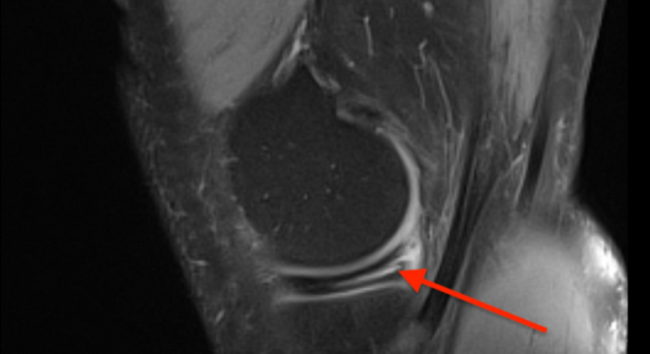

Chonodromalacja – uszkodzenia chrząstki

Powracam z tematem chrząstki stawowej. Informacja o uszkodzeniu chrząstki deprymuje pacjenta, a w szczególności sportowca. Jest on jednak pełen wiary w możliwość medycyny i leczenia. Niestety sprawa jest bardzo złożona… Nieleczone uszkodzenia chrząstki prowadzą do zniszczenia stawu, a w konsekwencji do ograniczenia jego funkcji i ograniczenia ruchomości.